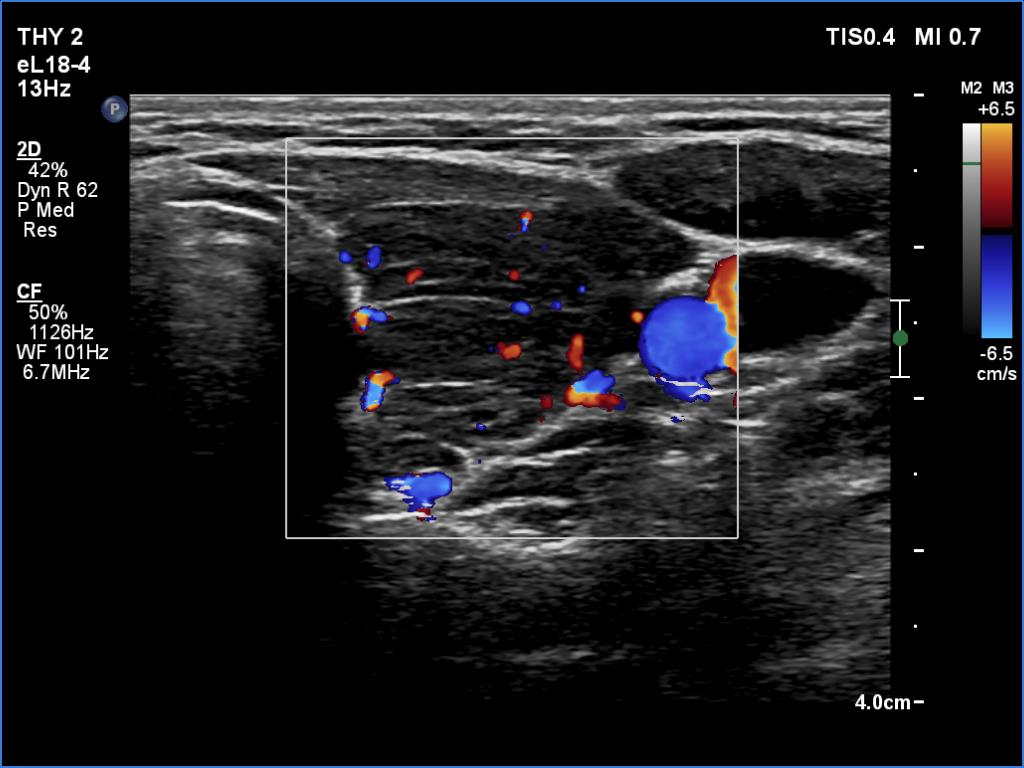

Left lobe, transverse scan, color Doppler mode. The vascularization is average.